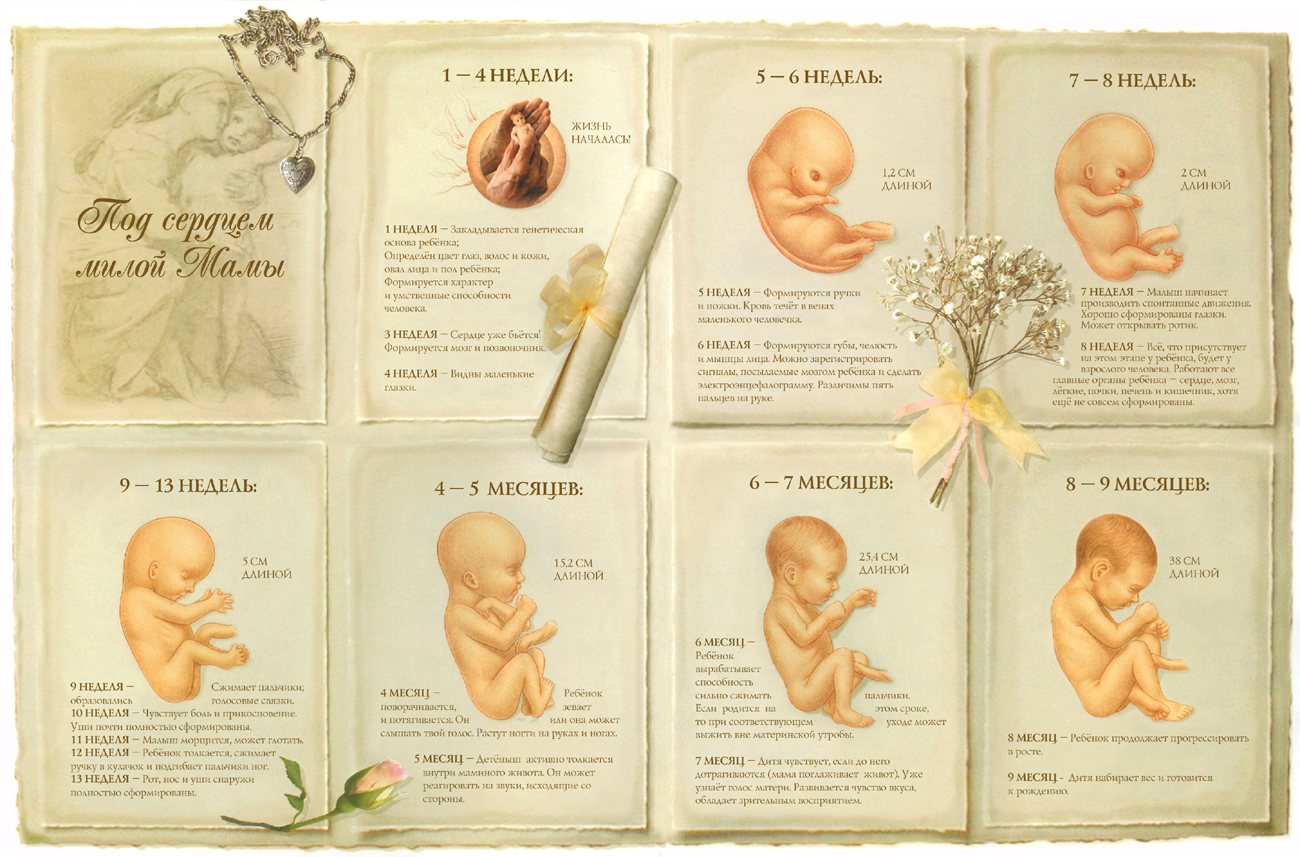

Формирование Плода в Первом Триместре: Важные Этапы